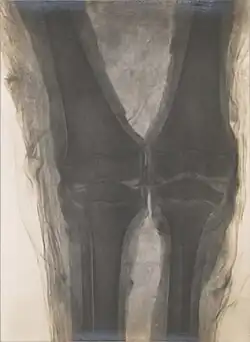

The first X-ray of a mummified Egyptian showing the knees of a child mummy in the collection of Naturmuseum Senckenberg[49]

In addition to sources by ancient writers and modern scientists, a better understanding of the Ancient Egyptian mummification process is promoted through the study of mummies. The majority of what is known to be true about the mummification process is based on the writing of early historians who carefully recorded the processes—one of whom was Herodotus. Now, modern day archaeologists are using the writings of early historians as a basis for their study. The advancement of new technology including x-rays has allowed for the analysis of mummies without destroying the elaborate outer wrappings of the body. In addition to the use of x-rays, autopsies are also being performed in order to gain a better understanding of the diseases suffered by Ancient Egyptians as well as the treatments used for these diseases. A pregnant mummy sheds light on pregnancy complications and prenatal care and treatments.[50][51] In learning their age of death, experts are able to create a timeline of the dates regarding the ruling of Egyptian kings. In looking at the bones of the mummified bodies, experts get a better idea of the average height and life span. Studying Ancient Egyptian Mummies, archaeologists are able to learn about the past.